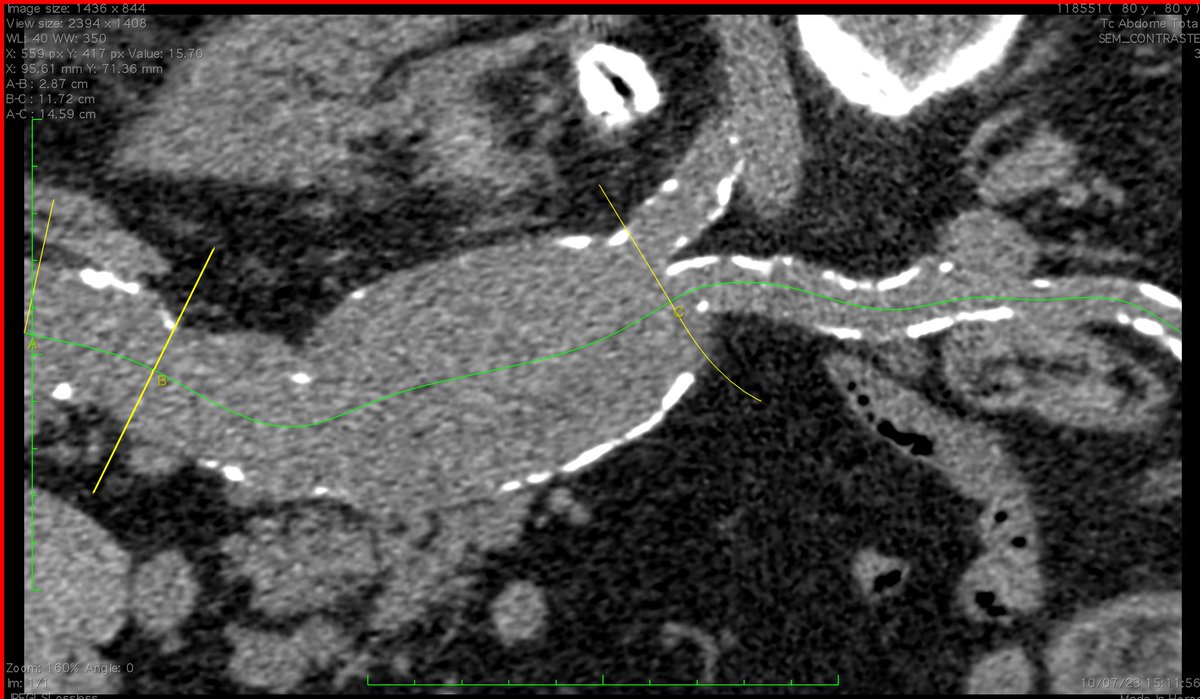

FEVAR with Diameter Reducing Ties plus 4 preloaded through-and-through wires for a small lumen case. Access from above. #AortaEd @gracemulatti @paulomenezesf @cfbechara @fonseca_alan5 @AndrePoci

@AndrePoci Congratulations! Beautiful neck. Diseased bifurcation. Tube or bifurcated?

@seleno_glauber We were able to do the infrarenal clamping, it was a stable paciente non rupted.

@AndrePoci Did you achieve a infrarenal approach at first attempt or begun with a supraceliac clamping?

PS: I’ve never seen such a left kidney displacement. Amazing.